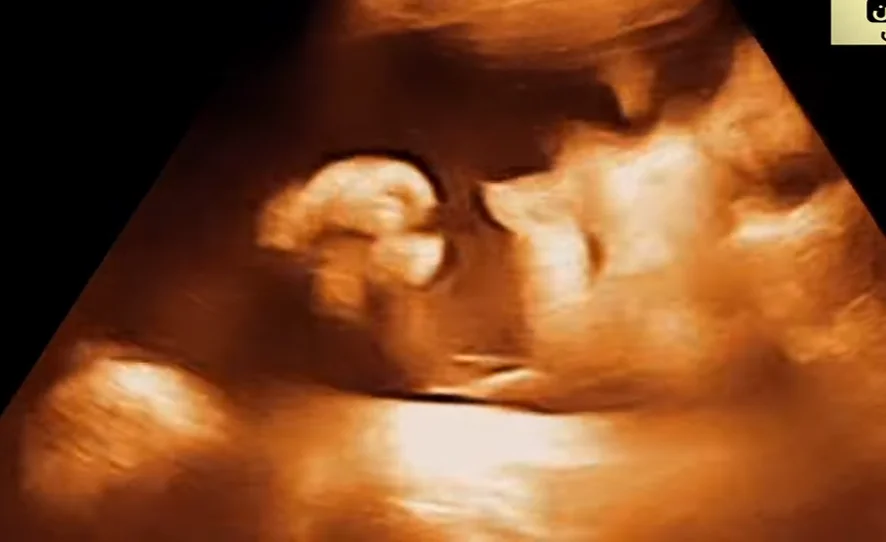

Hội chứng Beckwith-Wiedemann vùng đầu mặt (BWS)